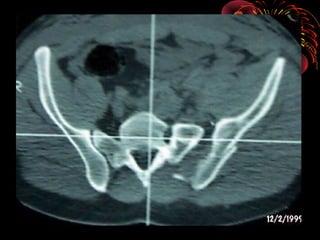

RADIOLOGÍA

• LA IMAGENOLOGIA NO DEBE RETRASAR MANEJO

INICIAL

• TIPO DE IMÁGENES ESTA DADO POR MECANISMO,

GRAVEDAD Y CAPACIDAD DEL CENTRO

• PARTIR DE UNA RX. A.P. PARA DIAGNÓSTICO

• COMPLEMENTARIS : 60°”E”-30°”S” Y OBLICUAS

• TAC : Herramienta de elección en fx. de pelvis

permite evaluar el compromiso óseo, fragmentario,

grados de desplazamiento, compromisos

abdominopélvicos y diferenciar hematomas retro e

intra abdominales

• Uretrocistograma en caso de hematuria franca

• Angiografía :evidencia de hematom retroperitoneal

y perdida de mas de 4 unidades de GR

TAC AXIAL DE PELVIS